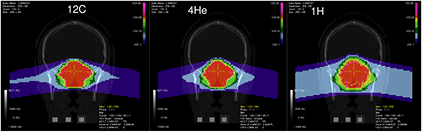

Radiotherapy is an essential component of cancer therapy. The combination of surgery, chemotherapy and radiotherapy is becoming a standard for most cancer patients. Out of the approximately 2/3 of cancer patients receiving radiotherapy, over 80% is irradiated with x-rays produced at linear electron accelerators (Linacs). The others receive specialized treatments such as gamma knife or brachytherapy. Only about 0.8% of the radiotherapy patients are treated with high-energy charged particles, but their number is rapidly increasing (figure 1). The rationale for using accelerated ions in therapy comes from the depth-dose distribution (figure 2), and was originally proposed by Wilson (1946), a student of Ernest Orlando Lawrence at the University of California in Berkeley (CA, USA). The advantages of the Bragg peak shown in figure 2 are quite obvious: unlike x-rays, the energy deposited per unit track increases with depth, therefore for a single beam the dose to the normal tissue will be much lower for ions than for photons when delivering the same dose to the tumor. While in x-ray therapy it is necessary to cross-fire the tumors from many different angles to increase the ratio of the doses to the tumor and normal tissues, only a few beams are necessary if charged particles are used (figure 3). Thus, the same radiation dose to the tumor (and therefore the same tumor control probability, TCP) can be achieved with lower integral dose to the normal tissue (lower normal tissue complication probability, NTCP); or the dose to the tumor can be increased (higher TCP) keeping the same NTCP as expected for x-rays. The most advanced x-ray delivery techniques, such as the intensity modulated radiotherapy (IMRT)5, are almost unbeatable in terms of target coverage, but the cost is an even higher 'dose bath' where the patient is immersed.

Both the longitudinal and lateral dose profiles (figure 4) resulting from the interaction of charged particles with the human tissues are important in CPT. The longitudinal profile is dominated by the inelastic electromagnetic interaction with atomic electrons, leading to a slow down of the primary particles. Lateral profile is mostly caused by the elastic scattering on target nuclei, and leads to a broadening of the beam. Nuclear interactions reduce the intensity of the primary beam and contribute to both longitudinal and lateral profiles.

Standard image High-resolution imageGenerally speaking, these processes (described in section 3) are fairly well understood, even if often not with the accuracy desirable for cancer therapy. The particle range, which is essential for irradiating the tumor, and not the surrounding organs at risk (OAR) in the Bragg peak region, can be calculated by the stopping power. As shown in figure 2(B), the narrow pristine Bragg peak must be extended to cover all the tumor area (spread-out-Bragg-peak, SOBP). This can be done either by passive modulation of the primary beam, or by changing the energy while raster scanning tumor slices with a pencil beam (figure 5). Scanning provides superior dose distributions compared to passive modulation, and greatly reduces the production of secondary neutrons, which may represent a risk for secondary cancers (see section 4.4). However, the interplay between pencil beam scanning and organ movement (figure 6) caused by breathing jeopardizes the dose distribution, and makes treatment of moving targets—e.g. lung tumors—with spot scanning much more complicated than with passive modulation (Bert and Durante 2011). The range uncertainty, due to organ movements and other causes (see section 5), requires to deliberately deliver a higher range as prescribed in order to avoid missing part of the tumor. This in turn can move the SOBP into an OAR, thus increasing toxicity. Lateral scattering broadens the beam and creates an undesired penumbra. Figure 7 shows that the penumbra is reduced by increasing the atomic mass of the ion used in therapy (see section 3.2). Nuclear interactions generate slow target fragments, which give a small contribution to the dose but can have high biological effectiveness. If particles heavier than protons are used, projectile fragmentation produces fast fragments with a mean velocity similar to the velocity of the primary ion. These fragments have lower mass and therefore higher range than the primary ions (see section 3.1), thus generating a longitudinal tail in the Bragg curve (figure 2). The angular distribution of the fragments is narrow in the forward direction, but the spread of the lighter fragments (protons and helium) contributes to the lateral widening of the beam.

Standard image High-resolution imageHirohiko Tsuji and other Japanese radiotherapists elected to use C-ions and started a program at the National Institute for Radiological Sciences (NIRS) in Chiba in 1994, with more than 8000 thousand patients treated to date for almost all kind of solid tumors in different regions (Tsujii et al 2014, Kamada et al 2015). The NIRS success led to a widespread use of carbon therapy in other heavy ion facilities in Asia and Europe. The USA is also planning a C-ion therapy facility in the near future, over 20 years after the termination of the clinical trial at the Lawrence Berkeley National Laboratory. However, other ions with 1 < Z < 6 (especially 4He) or slightly heavier than 12C (e.g. 16O) can play a role in CPT (see section 3.4).